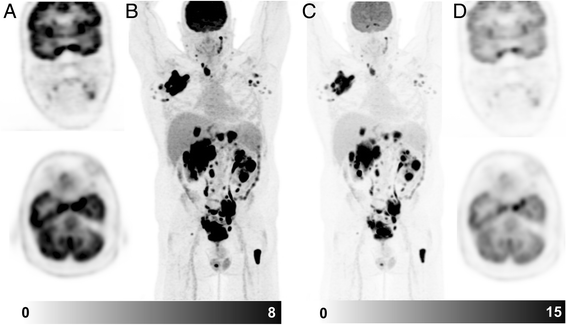

Since some disease processes can have extremely high SUV values, it may be necessary to increase the upper threshold to appreciate the dynamic range of glycolytic activity. This is particularly important in diseases where there can be considerable heterogeneity in disease. Follicular lymphoma, in which most lesions can have a SUVmax in excess of 10 but regions of high-grade transformation with corresponding values of >15, is a particular case in point. Standard thresholds provide a good representation of the extent of disease but using a higher upper threshold to display the images can help to identify the regions of likely transformation or different disease biology and can aid biopsy site selection (Fig. 2).

This patient presented with suspected metastatic nasopharyngeal cancer. Initial workup with endoscopic ultrasound and biopsy of the subcarinal node was non-diagnostic with necrotic tissue. FDG PET/CT demonstrates very intense uptake at all sites with lower uptake in the subcarinal node, only evident when widening the PET window. The findings suggest a different tumour biology at this site  with necrosis. When feasible, we recommend biopsy of the most FDG-avid lesion which likely represents the site of most aggressive disease and least likely to be non-diagnostic. In summary, the PET study windowed narrowly is primed for sensitivity whereas a wider window enables superior characterisation